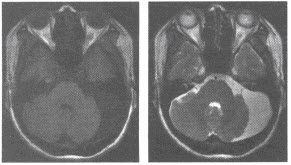

通过设定MRI的成像参数(TR和TE),TR是重复时间即射频脉冲的间隔时间,TE是回波时间即从施加射频脉冲到接受到信号问的时间,TR和TE的单位均为毫秒(ms),可以做出分别代表组织Tl或T2特性的图像(T1加权像或T2加权像;通过成像参数的设定也可以做出既有Tl特性又有T2特性的图像,称为质子密度加权像。三、MRI在临床的应用表现在哪些方面?磁共振成像的图像与CT图像非常相似,二者都是“数字图像”,并以不同灰度显示不同结构的解剖和病理的断面图像。

磁共振成像术的空间分辨室,也有待进一步提高。(一)颅脑与脊髓 MRI对脑肿瘤、脑炎性病变、脑白质病变、脑梗塞、脑先天性异常等的诊断比CT更为敏感,可发现早期病变,定位也更加准确。

对颅底及脑干的病变因无伪影可显示得更清楚。MRI可不用造影剂显示脑血管,发现有无动脉瘤和动静脉畸形。

不仅可显示灰质,白质,还可显示一些神经核,甚至可识别出脑神经,视神经及传导束。三维成像和流空效应,对病变定位不仅准确,还可了解病变与血管关系,给病变定性提供诊断依据。

不仅可显示灰质,白质,还可显示一些神经核,甚至可识别出脑神经,视神经及传导束。三维成像和流空效应,对病变定位不仅准确,还可了解病变与血管关系,给病变定性提供诊断依据。